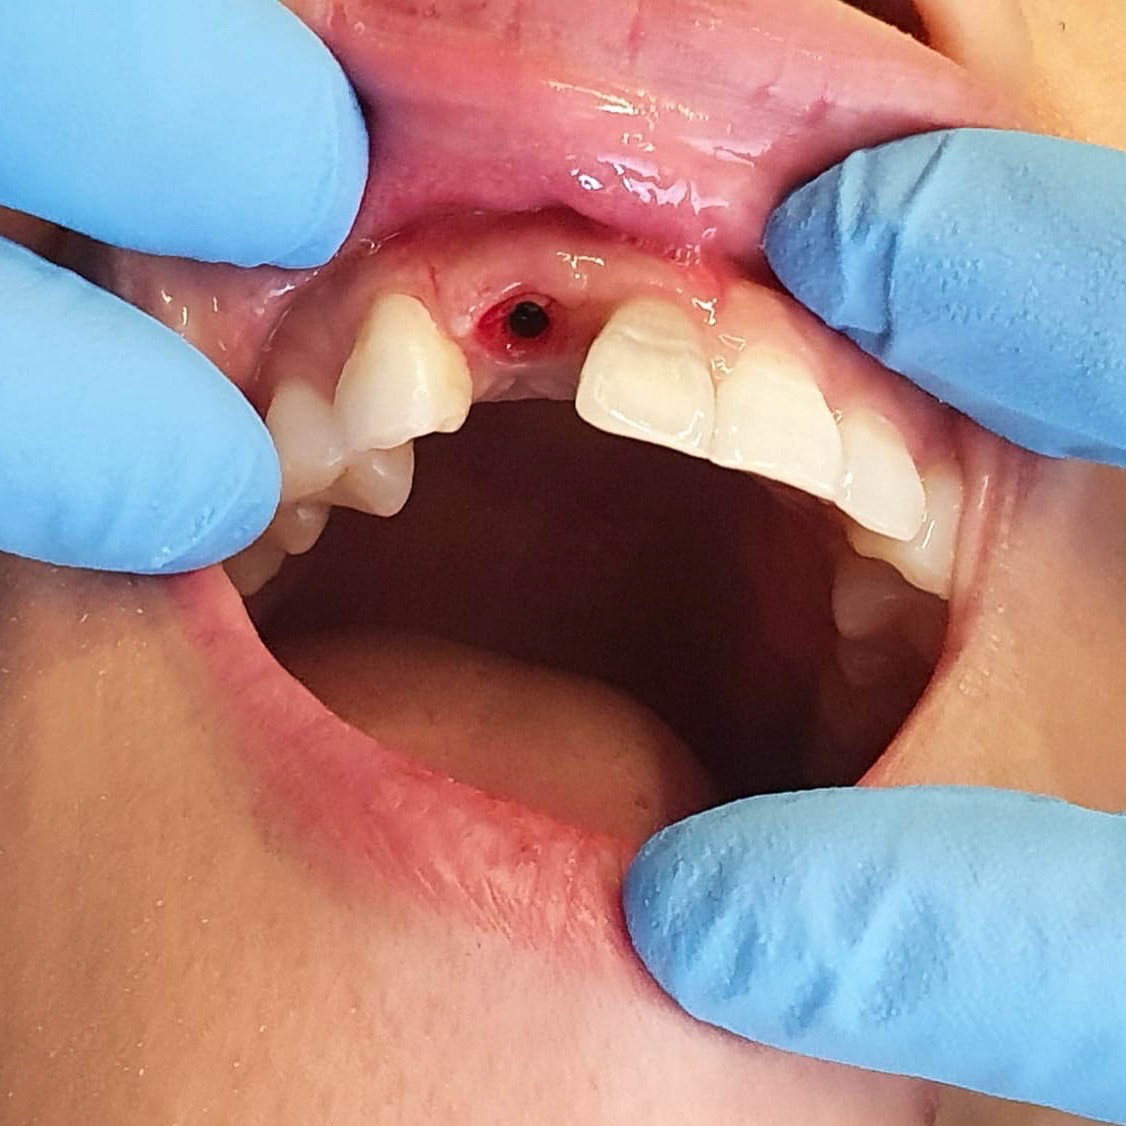

Implantologie

Wenn Zähne verloren gehen, ermöglichen Implantate diesen Verlust wieder auszugleichen. Mit Hilfe moderner Methoden und natürlich aussehenden Materialien lässt sich heute der professionelle Zahnersatz kaum noch von den echten Zähnen unterscheiden. Als eine Art Fundament für den neuen Zahnersatz können diese Implantate verstanden werden und sind dadurch extrem vielseitig zu verwenden. Sowohl für einzelne als größere Lücken können sie eingesetzt werden und bilden die Basis für den späteren Zahnersatz.

Implantation: Wir bieten Ihnen Vollkeramikimplantate, vollständig metallfreier Zahnersatz vom Implantat bis zur Krone.

Knochenaufbau / Augmentation

Sollte nicht genügend Knochen an einer Stelle im Kiefer vorhanden sein, kann dieser entweder in einer vorbereitenden OP oder zeitgleich mit dem Implantat aufgebaut werden. Sogar verloren gegangene Knochen- oder Zahnfleischsubstanz kann heute wieder aufgebaut werden.

Bei solch einem Eingriff spricht man von einer Augmentation oder auch einfach, Knochenaufbau. Dabei wird im Oberkiefer vom Sinuslift gesprochen, welcher offen oder geschlossen operiert werden kann. Welche Technik gewählt wird ist immer individuell vom Patienten und dessen Defekt abhängig. Die Beratung über die verschieden Verfahren werden Ihnen genau erläutert.